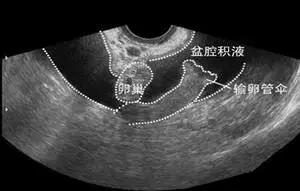

每天就诊的患者中 ,有相当一部分女性朋友做完超声,都会拿着报告单,焦急的问我:大夫怎么会有盆腔积液了呢?以前做过超声都没有,我是不是得盆腔炎了?大多数情况下我都会回答,“不用担心,这种盆腔积液是生理性的,没事,不用管它”。 那我们了解一下“盆腔积液”是怎么一回事,首先它可以分成生理性和病理性的, 生理性盆腔积液不需要特殊治疗, 正常生理情况下盆腔内会存在有少量液体,主要作用是润滑脏器表面、减少脏器之间摩擦,而且还有一定的防御功能。在排卵期,卵泡破裂后卵泡液会流到盆腔内,此时彩超检查会提示盆腔少量积液,不需对此过分担心,可以自行吸收,不必进行治疗。  如果是病理性的如盆腔炎或者肿瘤性的积液,积液量都会在100毫升以上,需要根据病因采取针对性的治疗。 病理性盆腔积液是因为盆腔存在炎性渗出物,多发生在盆腔炎性疾病之后。盆腔炎性疾病(简称盆腔炎)是女性生殖道及其周围组织的炎症,主要包括子宫内膜炎、输卵管炎、输卵管卵巢脓肿、盆腔腹膜炎等,可遍及女性生殖器的多个部位。还有 宫外孕、卵巢囊肿破裂、黄体破裂导致盆腔内出血,B超提示多量盆腔积液。患者有急腹症表现,如腹痛,腹部压痛阳性、反跳痛阳性,如果超声示盆腔积液透声差,则常为血块,此时可行后穹窿穿刺,如抽吸出不凝血,则证明腹腔内出血。 虽然盆腔积液并不一定是盆腔炎,但盆腔炎能够诱发盆腔积液,如果彩超提示积液量较多、范围较大,且结合临床症状伴有单侧或双侧腹痛、腰骶部疼痛、发热、阴道分泌物过多、活动后腹痛加剧等症状,需警惕是否存在盆腔炎了,应及时到医院就诊,以免延误病情,造成病菌迅速扩散,导致输卵管炎及输卵管堵塞等并发症,甚至不孕症或慢性盆腔痛等等。 正确认识盆腔积液,规范治疗盆腔炎,当然更重要的是预防。日常生活中加强锻炼,保持心情愉快,少食生冷辛辣等刺激食物,注意个人生理卫生,经期避免*生活性**,注意避孕,避免盆腔操作手术,都可以使女性朋友远离盆腔炎。